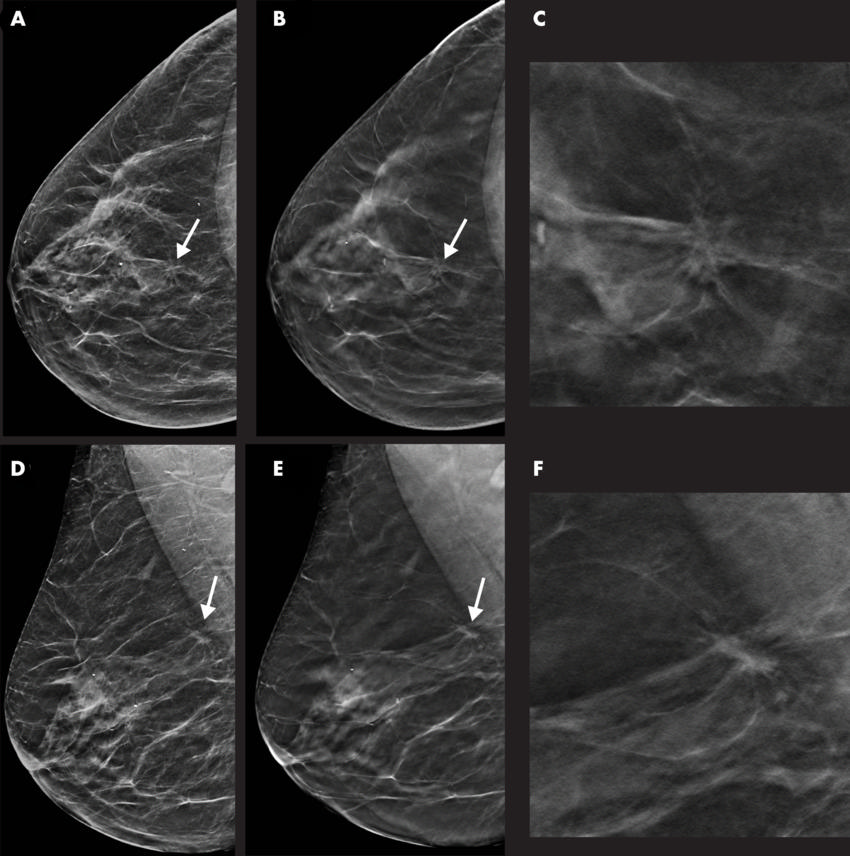

Figure 3. Images in a 55-year-old woman with a spiculated mass localized in the upper central quadrant (arrow in A, B, D, and E) of right breast detected with digital breast tomosynthesis (DBT) plus synthetic mammography (SM). Breast density was classified as category C with the Breast Imaging Reporting and Data System. Mass was invasive ductal carcinoma, stage I, and was estrogen and progesterone receptor positive and human epidermal growth factor receptor 2 negative. A, Image from SM in craniocaudal view. B, Single-slice DBT image in craniocaudal view. C, Magnification of the lesion depicted in B. D, Image from SM in mediolateral oblique view. E, Single-slice DBT image in mediolateral oblique view. F, Magnification of the lesion depicted in E.